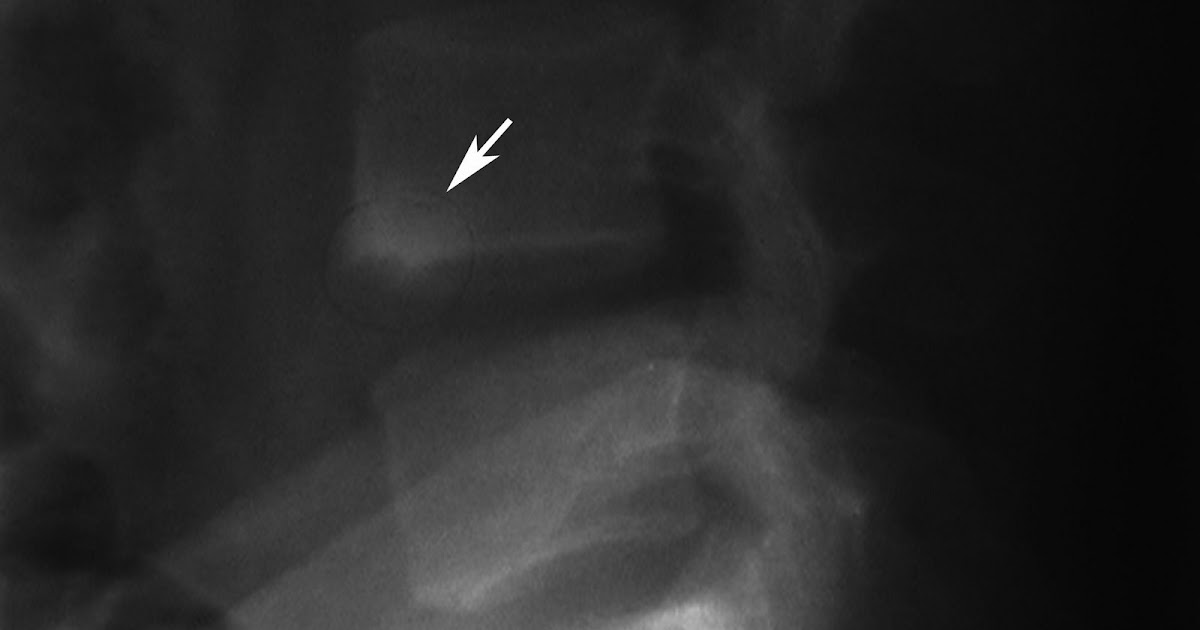

Ankylosing spondylitis. Lateral lumbar spine radiograph shows sclerosis

Ankylosing spondylitis. Lateral lumbar spine radiograph shows sclerosis Corner Sign Bone The areas are surrounded by reactive sclerosis and have. The mr corner sign was defined as being a triangular or quadrant, sharply marginated, corner abnormality of the discovertebral junction unassociated with endplate erosion, osteophytes,. It is a pathognomonic sign of. The wimberger sign, also called wimberger corner sign, refers to localized bilateral metaphyseal destruction of the medial proximal tibias. The. Corner Sign Bone.